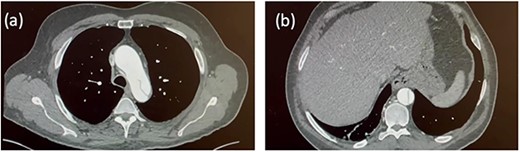

Seven days later, a repeat CT aorta angiogram showed that the dissection had extended into the left common carotid artery (Fig. 2). The ascending aorta had further dilated (51 × 54 mm) due to retrograde dissection extending into the aortic root. The patient was now diagnosed with a Stanford type A aortic dissection involving the aortic root, ascending aorta and aortic arch. He was scheduled for complex emergency proximal thoracic aortic reconstructive surgery. The patient’s bloodwork was sent for routine pre-operative testing.

Follow-up CT aortogram. Aortic dissection extending into the left common carotid artery and involving the left subclavian artery without compromising the lumen. The ascending aorta has further dilated from Fig. 1 to now measure ~51 mm.